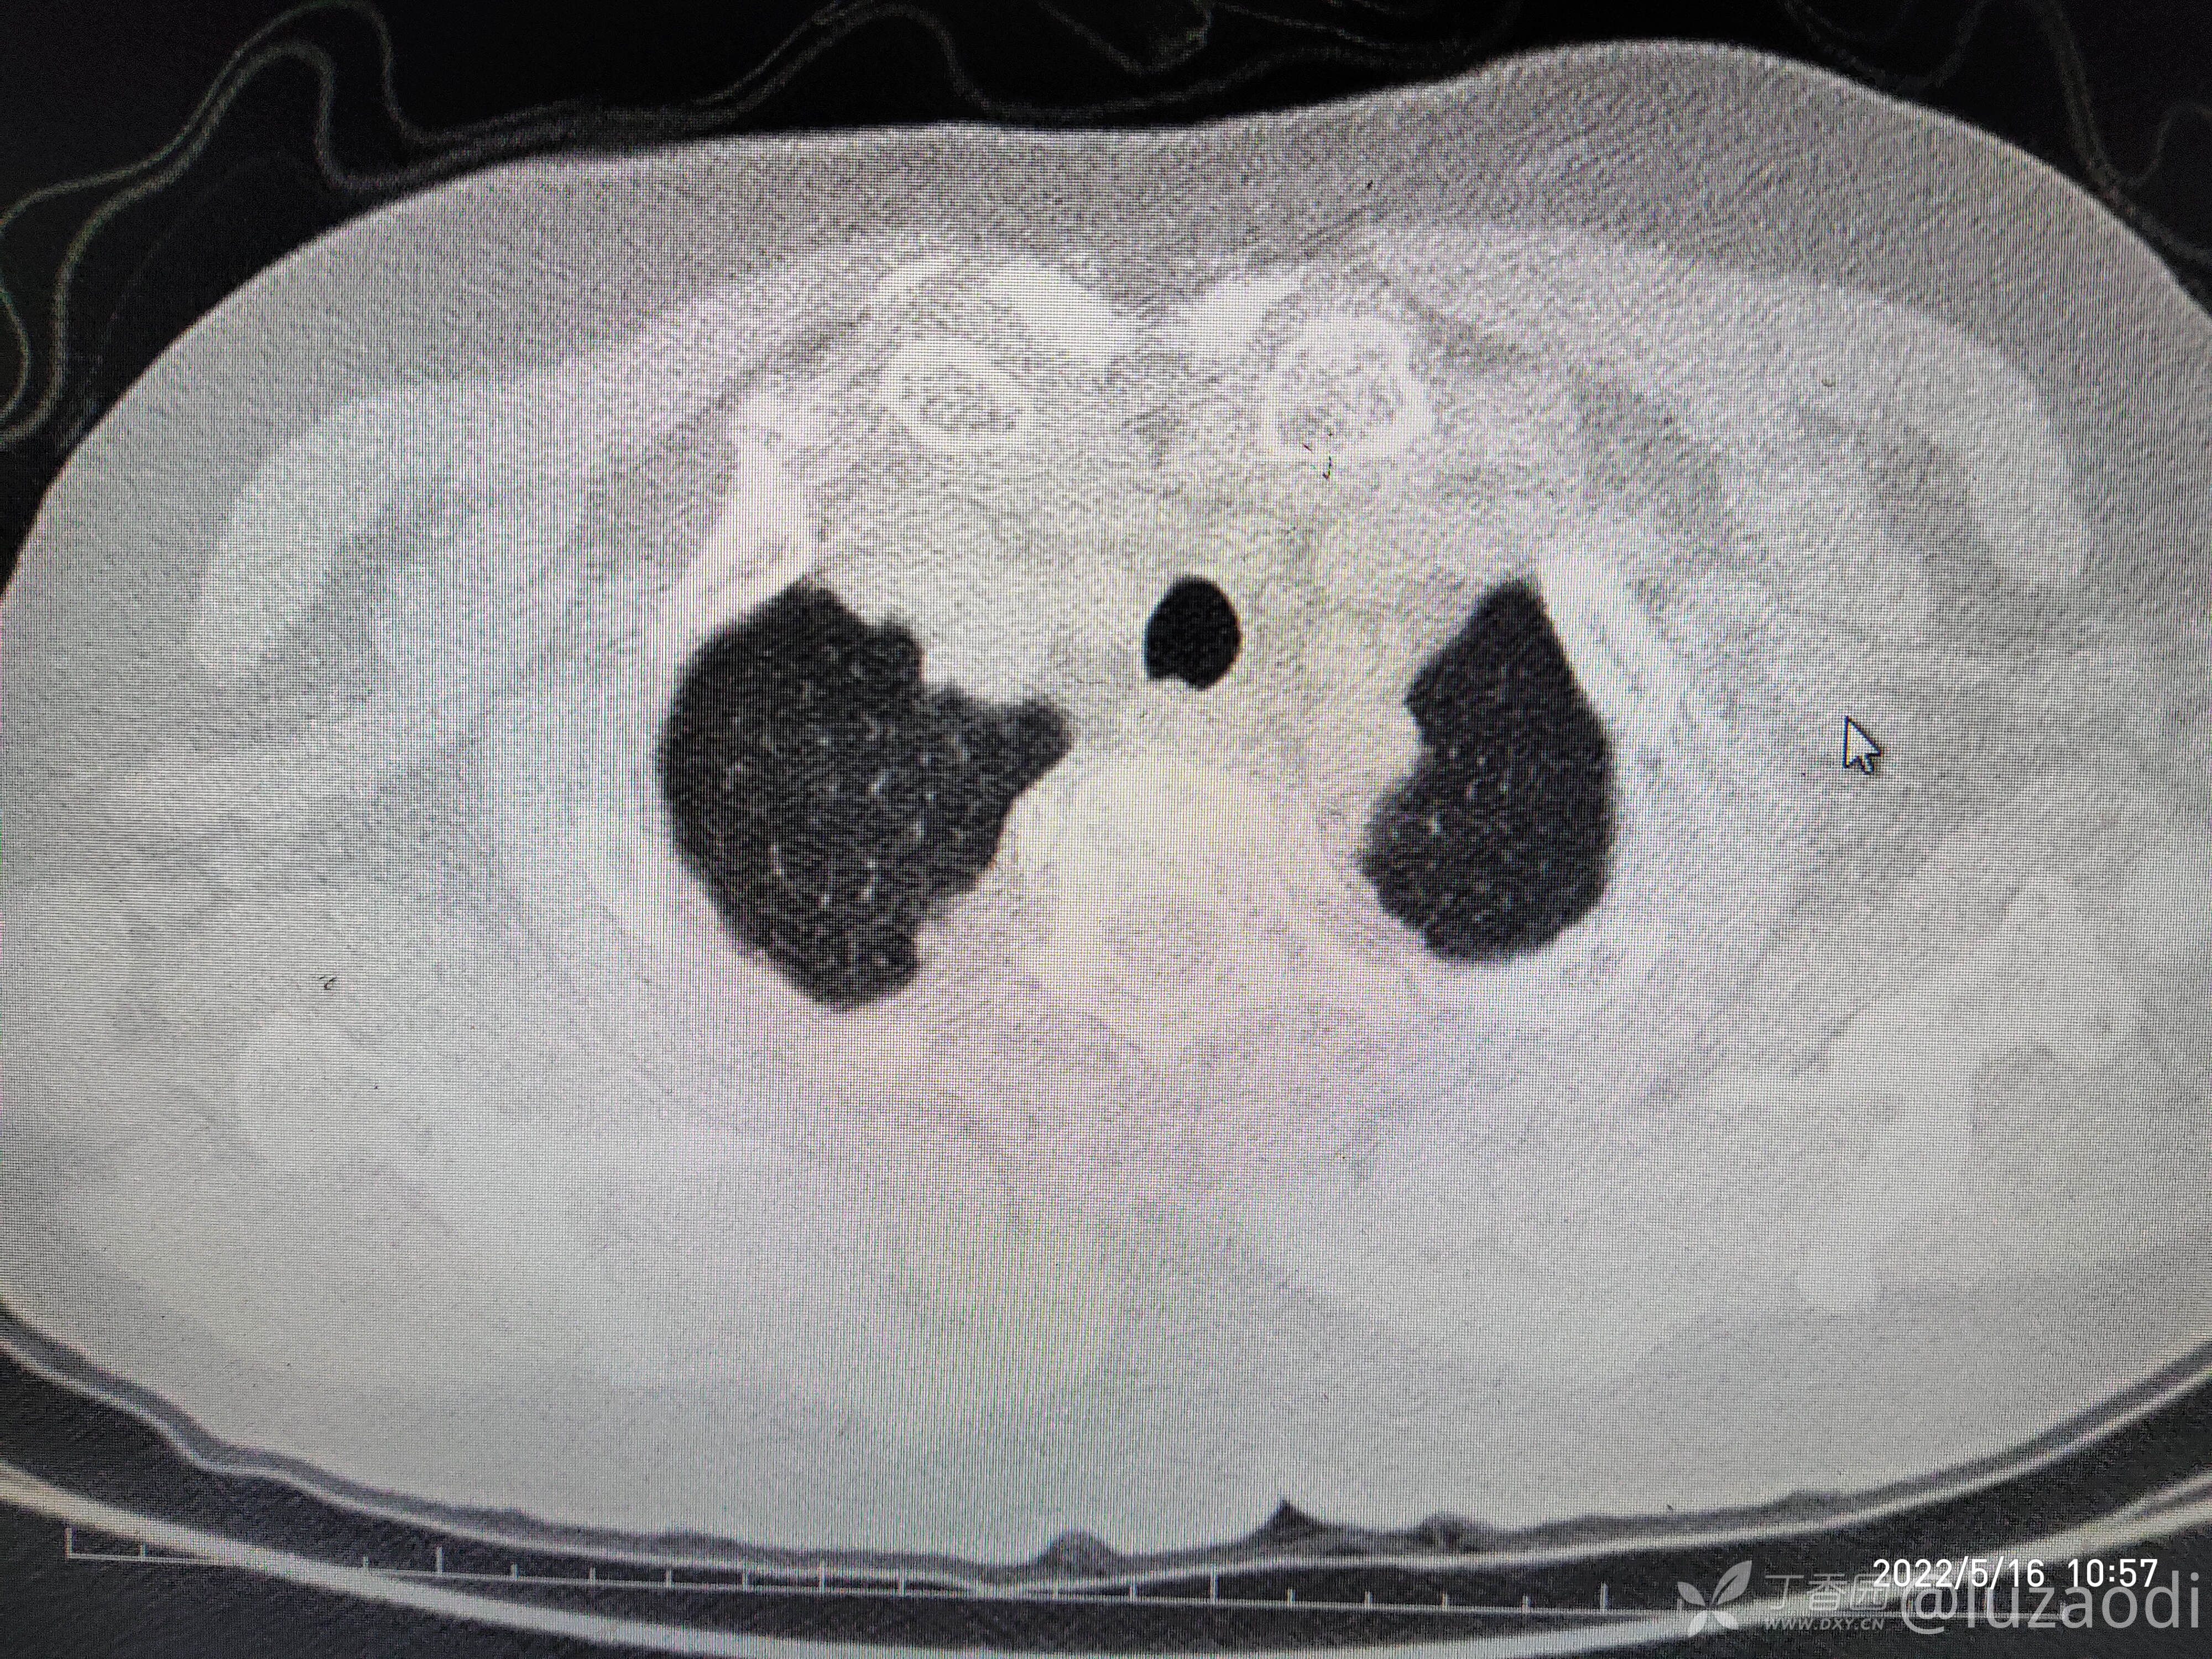

治疗经过:入院后患者仅有乏力,未见明显神经定位征。近期无发热、咳嗽、腹泻症状。遂予血糖、心电图、生化检查及影像检查,结果如下:

心电图将就着看,因为是手机拍的。

我去。。。。。视频只能上传一个,头颅CT上传不了,我直接说报告吧。头颅CT报腔隙性脑梗。